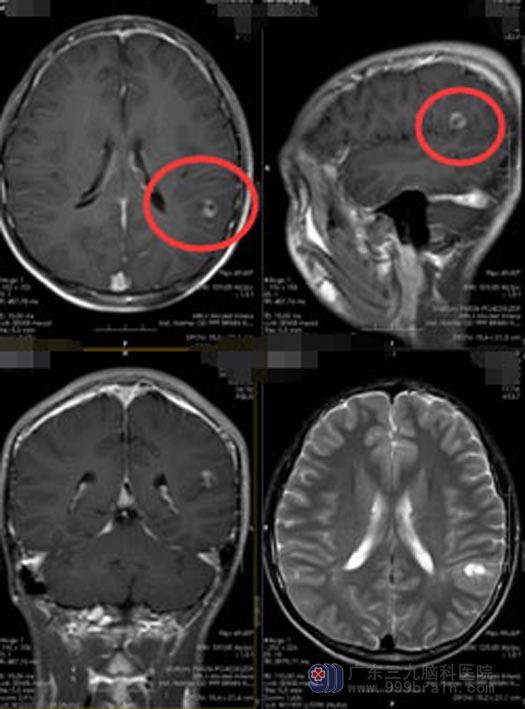

2周前,阿康再一次癫痫发作,检查头颅MRI,结果提示:左侧额叶占位。在广东三九脑科医院进一步头颅MRI检查,显示“左侧颞顶叶占位性病变”,结合阿康的临床症状,医院副院长、神经外五科主任鲁明认为患者颅内病变属于肿瘤性病变,初步怀疑是低级别胶质瘤,术前脑电图也考虑患者的癫痫是低级别胶质瘤所致。鲁明建议尽快进行手术。

完善相关检查后,鲁明带领治疗团队为阿康行“左侧颞顶叶占位切除术”。神经功能导航准确定位,术中避开语言区、脑电图定位癫痫灶,将肿瘤全切并同时切除了癫痫灶。

术后,阿康生命体征平稳,神志清醒,四肢活动自如,对答清晰。无癫痫发作,语言功能正常。术后病理为节细胞胶质瘤。